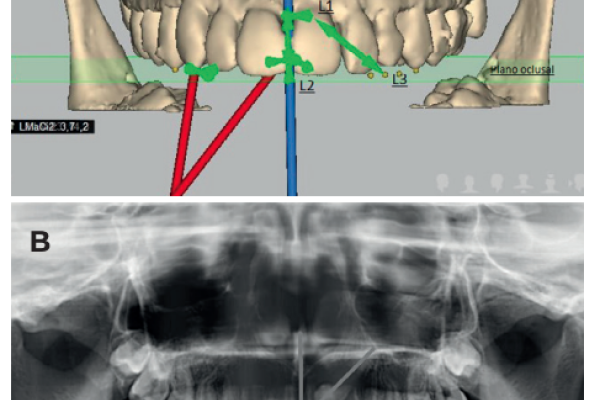

2 | ORIGINAL ARTICLE | RADIOGRAPHIC DIAGNOSIS OF IMPACTED MAXILLARY CANINES: COMPARISON BETWEEN TWO AND THREE DIMENSIONS |